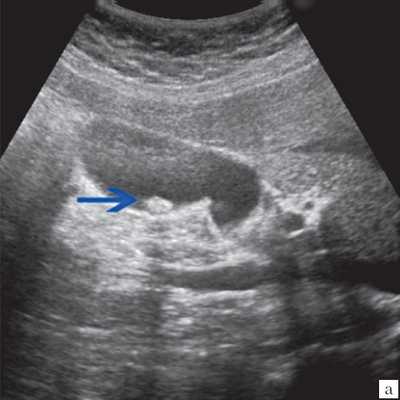

- Ультразвуковая диагностика. К визуализирующим методам диагностики холангита относятся УЗИ брюшной полости и печени, ультрасонография желчных путей. С их помощью удается получить изображение желчных протоков, выявить их расширение, определить наличие структурных и очаговых изменений в печени.

Клиническая картина желчнокаменной болезни многообразна [5-6, 10]. Условно выделяют хроническую болевую, хроническую рецидивирующую, диспептическую, стенокардитическую и ряд других клинических форм. Характерным ультразвуковым признаком конкремента в желчном пузыре является его акустическая тень. Такая тень возникает из-за высокой плотности камня по сравнению с мягкими тканями. Наличие или отсутствие тени помогает отличить камень от полипа желчного пузыря (рис. 4).

а) Одиночный конкремент желчного пузыря (подвижная гиперэхогенная структура, дающая четкую теневую дорожку).